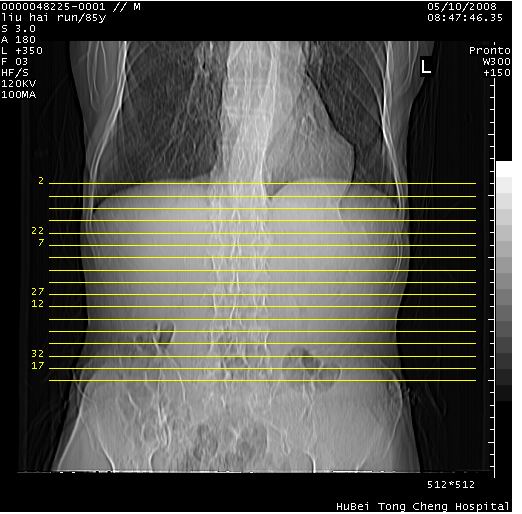

标题: CT13403:M,85Y。胆系低位梗阻。胰头占位? [打印本页]

标题: CT13403:M,85Y。胆系低位梗阻。胰头占位?

彩超示胰头实质欠均匀,胰管扩张。